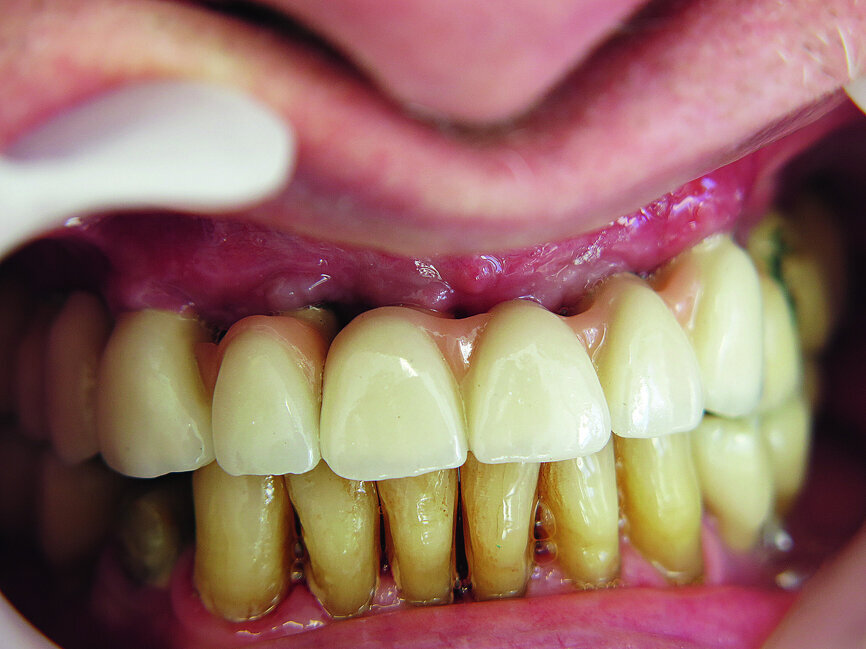

Fig. 12: Screwed on superstructure.

In two cases, a thickness flap was raised after 12 weeks in order to access the cover screw. In 85 % of cases implant stability was evaluated using resonance frequency analysis (Osstell ISQ). A healing abutment was placed and the flap was sutured using 4/0 sutures (RESORBA Medical). Finally, after nearly two weeks, a titanium abutment was placed and a cemented metal-ceramic restoration was fabricated.